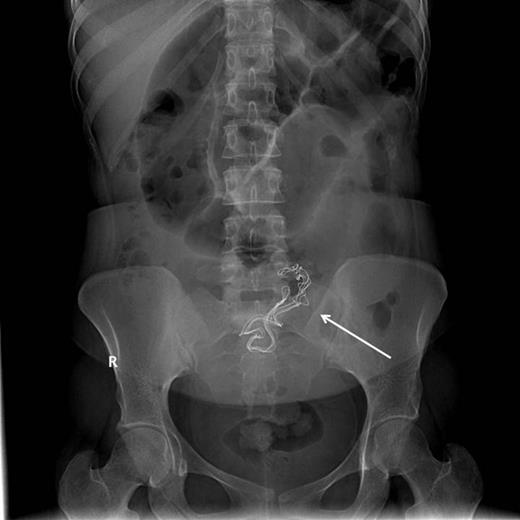

Upon admission, she was afebrile, vitally stable, and her abdomen was distended and tympanic. Bowel sounds were increased in frequency and pitch. Digital rectal examination showed normal-colored stool. Laboratory investigations showed a white blood cell count of 10 700 cells/ml and a sodium level of 123 mmol/l, while other biochemical parameters were within normal limits. Abdominal roentography revealed dilated small intestinal loops with a finding of a radio-opaque density in the abdomen (Fig. 2). A diagnosis of small intestinal obstruction most likely caused by retained surgical sponge was made. On abdominal exploration, the small intestine was dilated down to the ileum with an intraluminal mobile mass felt in the distal ileum (Fig. 3). Before proceeding for mass removal, at around 80 cm from the duodenojejunal junction, there were two adjacent segments of the jejunum adherent to each other and both were adherent to the peritoneal wall by fibrous adhesions. Consequently, adhenolysis, enterotomy and removal of the mass, which was manually pushed there (Fig. 4), followed by resection and anastomosis of the compromised jejunal segment, were achieved. The foreign body was found to be retained surgical sponge (Fig. 5). However, apart from the isolated area of adhesion, exploration of the rest of the abdominal cavity did not show any lesions in the peritoneal cavity or perforation or fistula or pelvic collection. The authors concluded that the transluminal migration of the sponge most likely occurred from that adherent part of the jejunum. The postoperative period was uneventful and the patient was discharged on the seventh day of her hospitalization in good condition.

Proximal small intestinal dilatation with the radio-opaque mark migrated proximally to the abdomen (arrow), indicating its mobile nature.